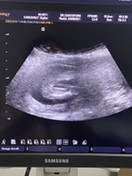

คุณหมอเดาว่าหนูเพศ หญิง ค่ะ🤰🏻👧🏻😁 ซาวด์ตอน15w6d คุณแม่ทีมสิงหารู้เพศกันหรือยังค่ะ😊 #ตอนนี้19w2dแล้วค่ะ😁 #ท้องแรก